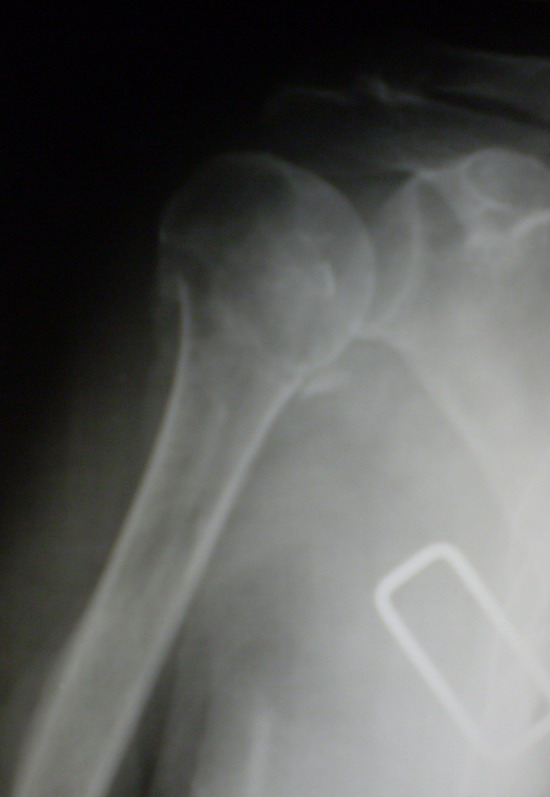

На 20-е сутки снял гипс, одел фиксирующюю ортопедическую повязку. Вот

контроль. Как видно, стояние хорошее, уже формируется костный мозоль.

Думаю еще недели 3 продолжать фиксацию.

Имя     : repozitcia, 20-e sutki.jpg